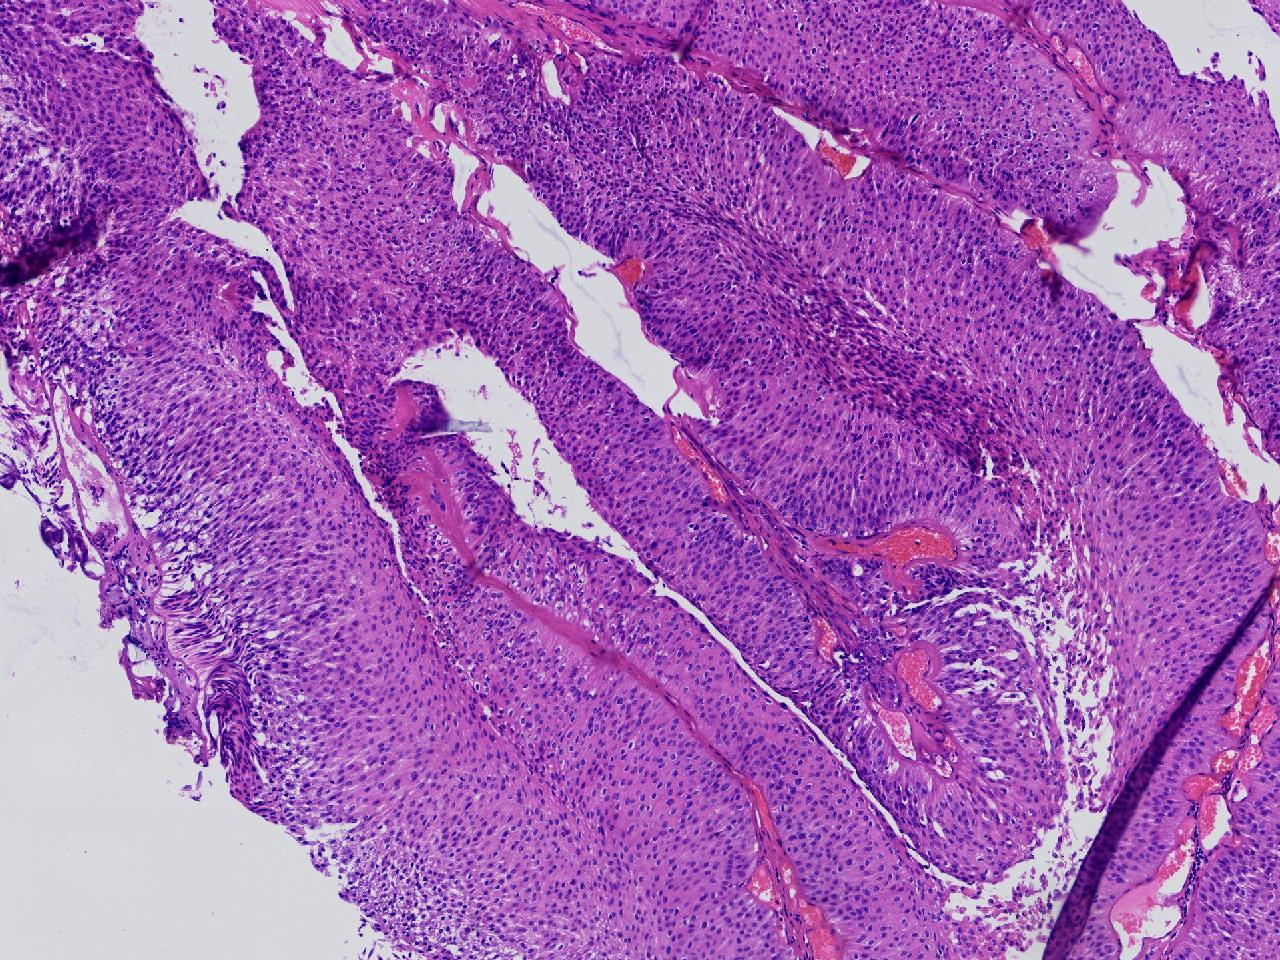

男,79岁,膀胱肿物。

膀胱肿物

灰白色不整形软组织多块,2X1X1厘米。

考虑:乳头状尿路上皮癌

乳头状尿路上皮癌,低级别。

这几张图片上没有看到明确的浸润。